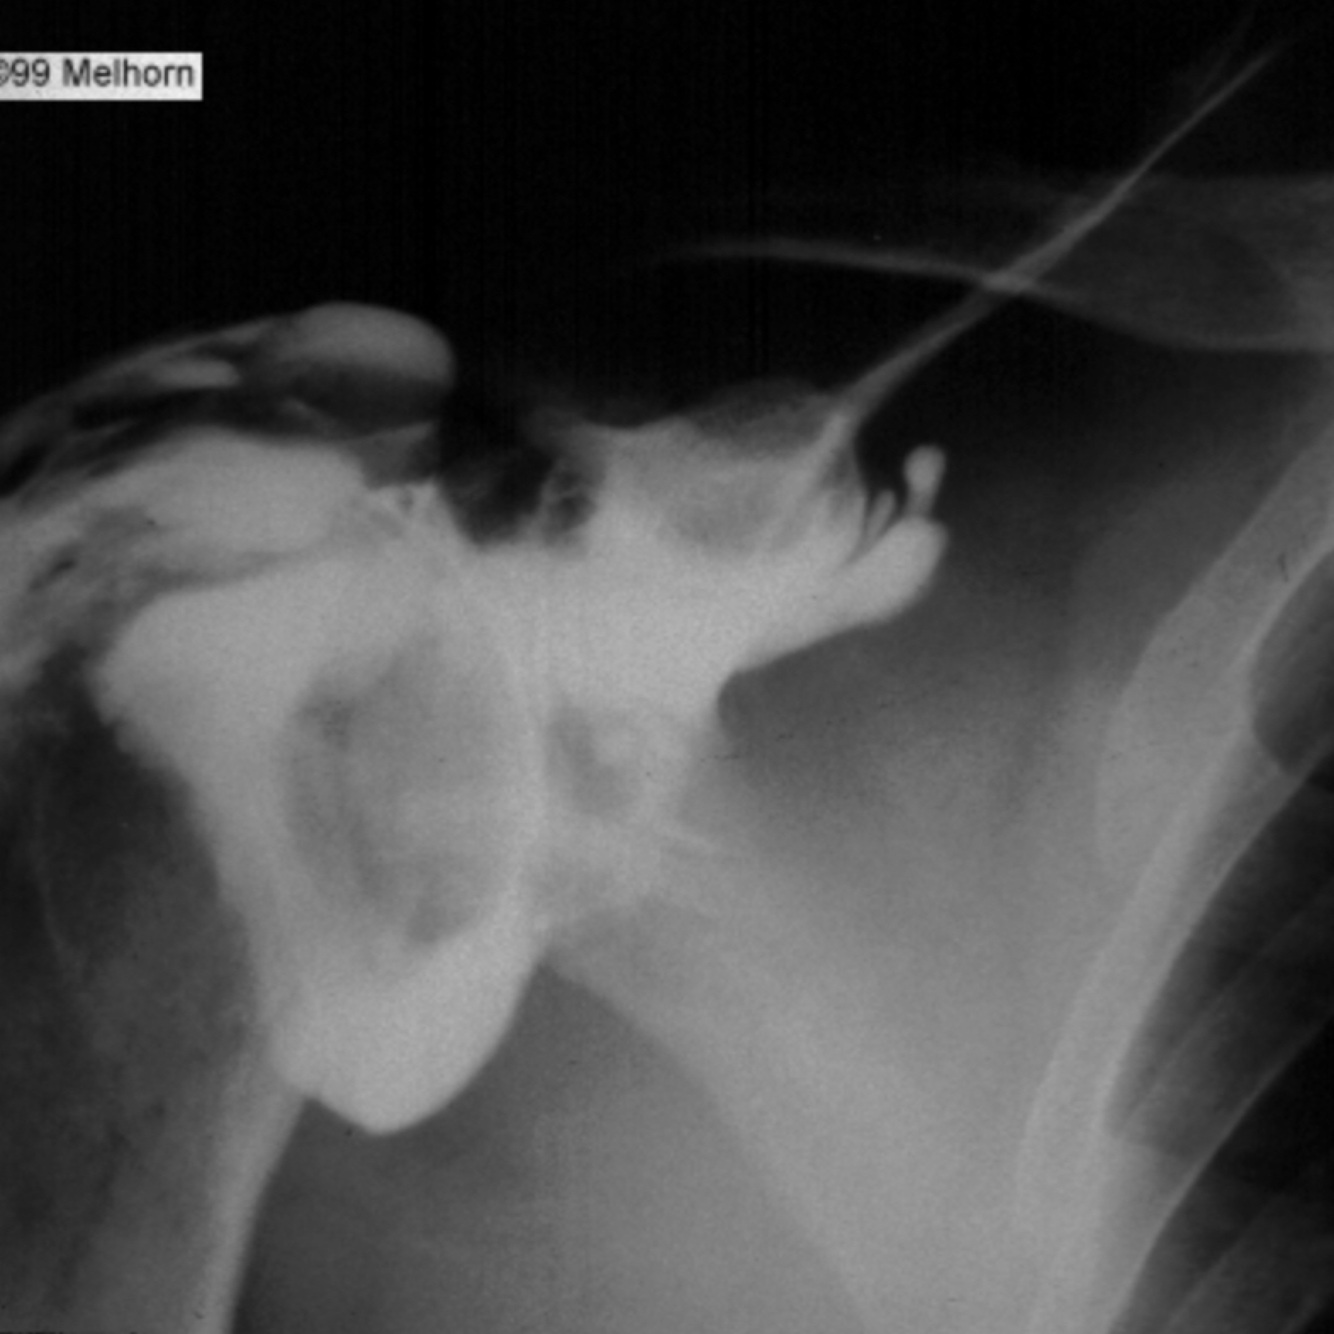

Femenino de 63 años de edad, con gonalgia y coxalgia bilateral, antecedente de prótesis de cadera derecha y rodilla izquierda, encuentra usted desviación de dedos de las manos hacia cubital, uso crónico de prednisona y sulfazalacina, llega a su consulta por dolor de hombro izquierdo de 6 meses de evolucion, intensidad 8/10, irradiacion hacia escapula, limita la flexion a tal grado que no logra peinarse, rotacion externa a 5°, rotacion interna 10°, con crepitos a la abduccion de 65°. Cuenta con el siguiente estudio de imagen:

En base a su sospecha diagnostica, ¿cual es el mejor tratamiento para esta paciente?

Pregunta 2 opciones:

Rehabilitación Física

Acromioplastía Anterior con Osteotomía Tipo Munford

Reemplazo Protésico de Humero Proximal

Movilización Bajo Anestesia

A

Remplazo protésico de húmero proximal